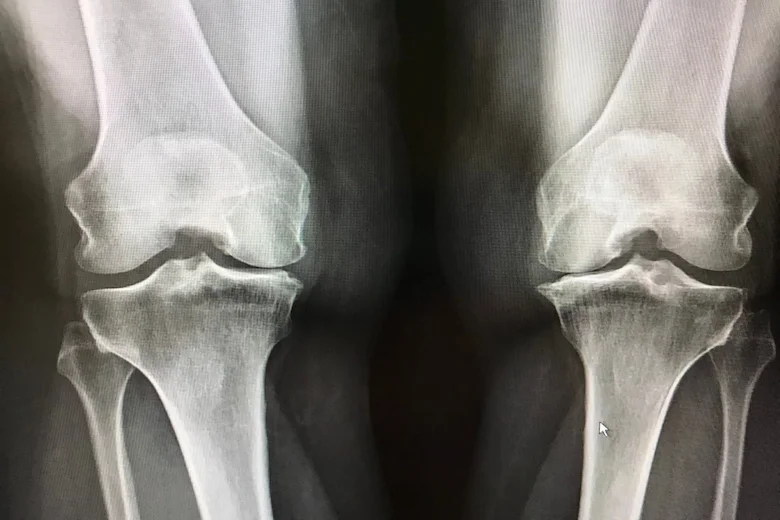

آرتروز زانو یکی از شایعترین بیماریهای مفصلی است که در اثر فرسایش تدریجی غضروف مفصل زانو و کاهش مایع روان کننده میان استخوانها به وجود میآید و معمولا با افزایش سن، اضافه وزن، آسیبهای ورزشی یا استفاده غلط و طولانی مدت از مفصل تشدید میشود. در این بیماری، سطح غضروفی که نقش ضربه گیر دارد نازک میشود و استخوانها به شکل مستقیم روی هم ساییده میشوند. همین موضوع باعث درد مداوم، خشکی مفصل، تورم، محدودیت حرکتی و صدای تق تق هنگام حرکت میشود.

آرتروز زانو یک بیماری پیشرونده است، اما با تشخیص زود هنگام، کنترل وزن، انجام فیزیوتراپی تخصصی، تقویت عضلات اطراف زانو، تزریقهای درمانی و اصلاح سبک زندگی میتوان روند پیشرفت آن را کند کرد و کیفیت زندگی بیمار را به شکل قابل توجهی بهبود داد.